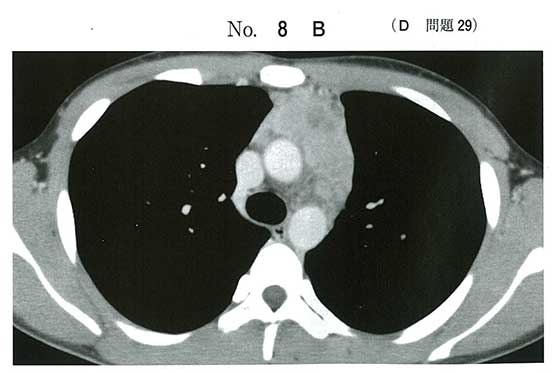

Eを測定する必要がない理由としては基本的にサルコイドーシスはBHLで、ほぼ両側性。少なくてもCTで右肺のリンパ節は腫れていないので不必要ってことかな?

eも実臨床では取りたい気がしますが、>>3,>>4にあるように、eが答えなのでしょう。たしかにあの位置はリンパ節腫脹ではなく、胸腺腫などを疑う位置ですから。

Eは画像からしてsarcoidosisのBHLの事を言ってるだろうからいい気がする。

画像が前縦隔腫瘍なので、サルコイドーシスのeにしました。

たしかに両側肺門リンパ節腫脹にも見えますが、前縦隔腫瘍を無視する必要はないと思います。